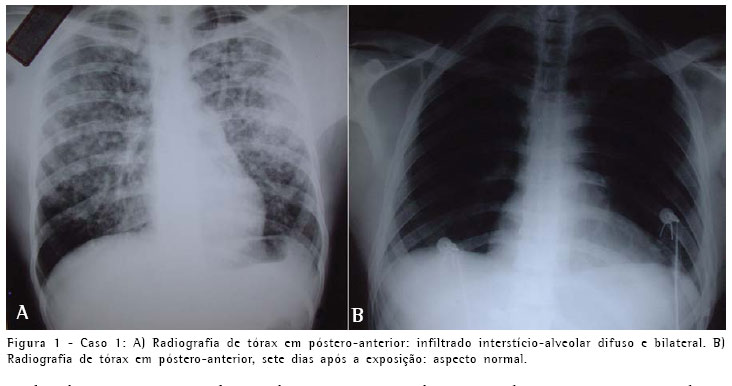

A radiografia simples do tórax, na admissão, mostrava infiltrado interstício-alveolar difuso (Figura 1). A gasometria com oxigênio por máscara facial a 8 l/min apresentou pH de 7,40, pressão arterial de oxigênio de 65 mmHg, pressão arterial de gás carbônico de 40 mmHg e saturação arterial de oxigênio de 92%. O teste rápido para o vírus da imunodeficiência humana foi negativo.

O quadro clínico e radiológico dos três pacientes foi compatível com edema pulmonar e insuficiência respiratória aguda. A evolução revelou-se favorável e no seguimento clínico, radiológico (Figuras 1, 2 e 3) e de função pulmonar por dezoito meses não apresentaram nenhuma repercussão respiratória.

O quadro clínico e radiológico dos três pacientes foi compatível com edema pulmonar e insuficiência respiratória aguda. A evolução revelou-se favorável e no seguimento clínico, radiológico e de função pulmonar por dezoito meses, não apresentaram nenhuma repercussão respiratória.